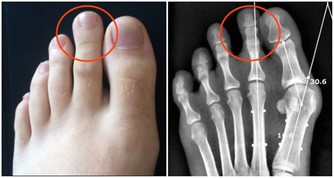

而喝酒臉紅正是因為體內缺乏將乙醛轉化為乙酸的酶,

導致乙醛在體內蓄積,損害肝臟功能,增加肝病風險,長期飲酒也會導致食道癌的發生。

美國《PlosMedicine》雜誌刊載了一篇名為《酒精性臉紅的反應:來自於飲酒關於食管癌未知的風險因素》的論文,美國國家酗酒與酒精中毒研究所和日本久里濱酒精過敏研究中心的研究人員的聯合研究發現,對於體內缺乏乙醛脫氫酶2或這種酶不能正常發揮作用的人群來說,患食道癌的風險隨酒精攝入量的增多而增大。

這種風險發生的機率的可能遠遠大於那些飲酒後“面不改色”的人群。喝酒臉紅的人,其實是不能喝,請不要再逼他們了。